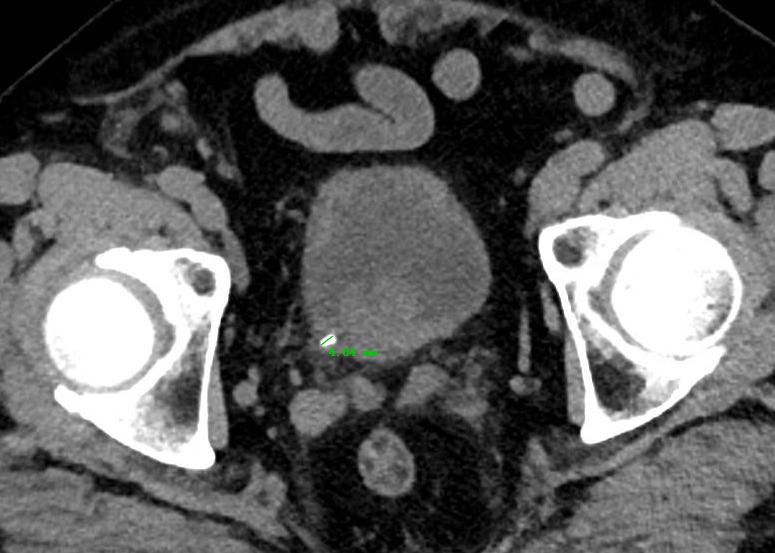

最近我们床位上遇到了一个 “老大难”患者 ,为什么说他是“老大难”呢?因为他有一颗输尿管结石, CT检查提示:左侧输尿管末端结石,结石直径4.84mm 。对于他的结石情况来说,的确最合适的 首选治疗方式就是通过药物的保守治疗方式 。但是一周下来,伴随着间断性的疼痛,在复查的时候发现结石并没有丝毫移动。

首先需要明确一点的是, 输尿管并不会自己长结石 。我们临床上最为多见的输尿管结石其实是肾结石掉落到输尿管以后换了一个名字而已。其实他的前身就是肾结石!

输尿管结石非常常见, 每11个人中就有1人患有泌尿系统结石疾病,并且更严重的问题在于,终生复发率约为50%。 输尿管结石常伴有明显症状,如肾绞痛和血尿。这也是为什么输尿管结石才会引起患者的高度重视的原因。因为疼痛让他们无法忍受!